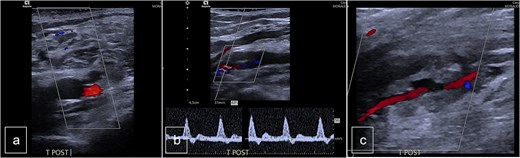

The patient was a 55-year-old female who was admitted to the Surgery Department due to recurrent bleeding and swelling at the surgical site following the removal of elective osteosynthesis material from the left tibia and patella by orthopedic surgeons. Initial investigation involved Doppler ultrasonography of the left leg, which revealed a large hematoma within the deep muscle structures of the proximal and middle thirds of the calf. An anechogenic pocket, exhibiting arterial flow on Doppler-color imaging, was identified, consistent with a pseudoaneurysm with dimensions of 28 × 20 × 24 mm, and it was supplied by arterial flow from the posterior tibial artery (PTA). The PTA remained patent distally but demonstrated a demodulated, monophasic flow with a velocity of 12 cm/s (Fig. 1).

Preoperative duplex sonography. (a) M-mode. Pseudoaneurysm of the posterior tibial artery (vascularized anechogenic pocket). (b) Doppler mode and (c) Doppler mode. Identification of communication with the medial wall of the PTA.